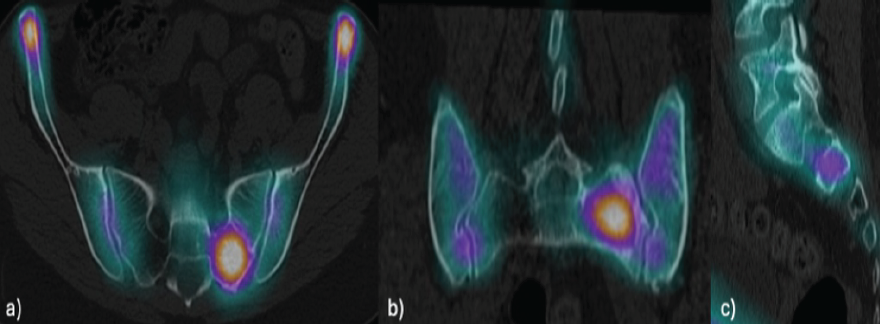

A 41-year-old female, with a history post-COVID immune dysfunction characterized by polyarthralgia, underwent a single photon emission computed tomography (SPECT-CT) scan, which revealed intense focal uptake in the left sacrum (Fig. 1), prompting the request for imaging studies with greater specificity.

Figure 1: Single photon emission computed tomography revealing intense focal uptake in the left sacrum, adjacent to S1 foramen in axial (a), coronal (b), and sagittal (c) views.